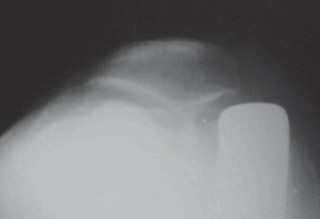

الأشعة السينية العادية (Plain Radiographs):

- المنظر الأمامي الخلفي (AP): يُظهر الركبة من الأمام.

- المنظر الجانبي (Lateral): يُظهر الركبة من الجانب.

- المنظر الخلفي الأمامي المثني (PA Flexed): يسمح بتقييم أفضل للجزء الخلفي من الركبة وقد يكشف عن تغيرات أكبر في الحجرة الخلفية الوحشية.

- منظر شروق الشمس (Sunrise/Patellofemoral): لتقييم المفصل الرضفي الفخذي.

- الأشعة السينية الطويلة للطرف السفلي بالكامل (Full-length standing radiographs): من الورك إلى الكاحل، وهي مفيدة جدًا، خاصة إذا تم استخدام تقنيات الملاحة الحاسوبية. تُظهر هذه الأشعة المحاذاة الكلية للطرف السفلي.